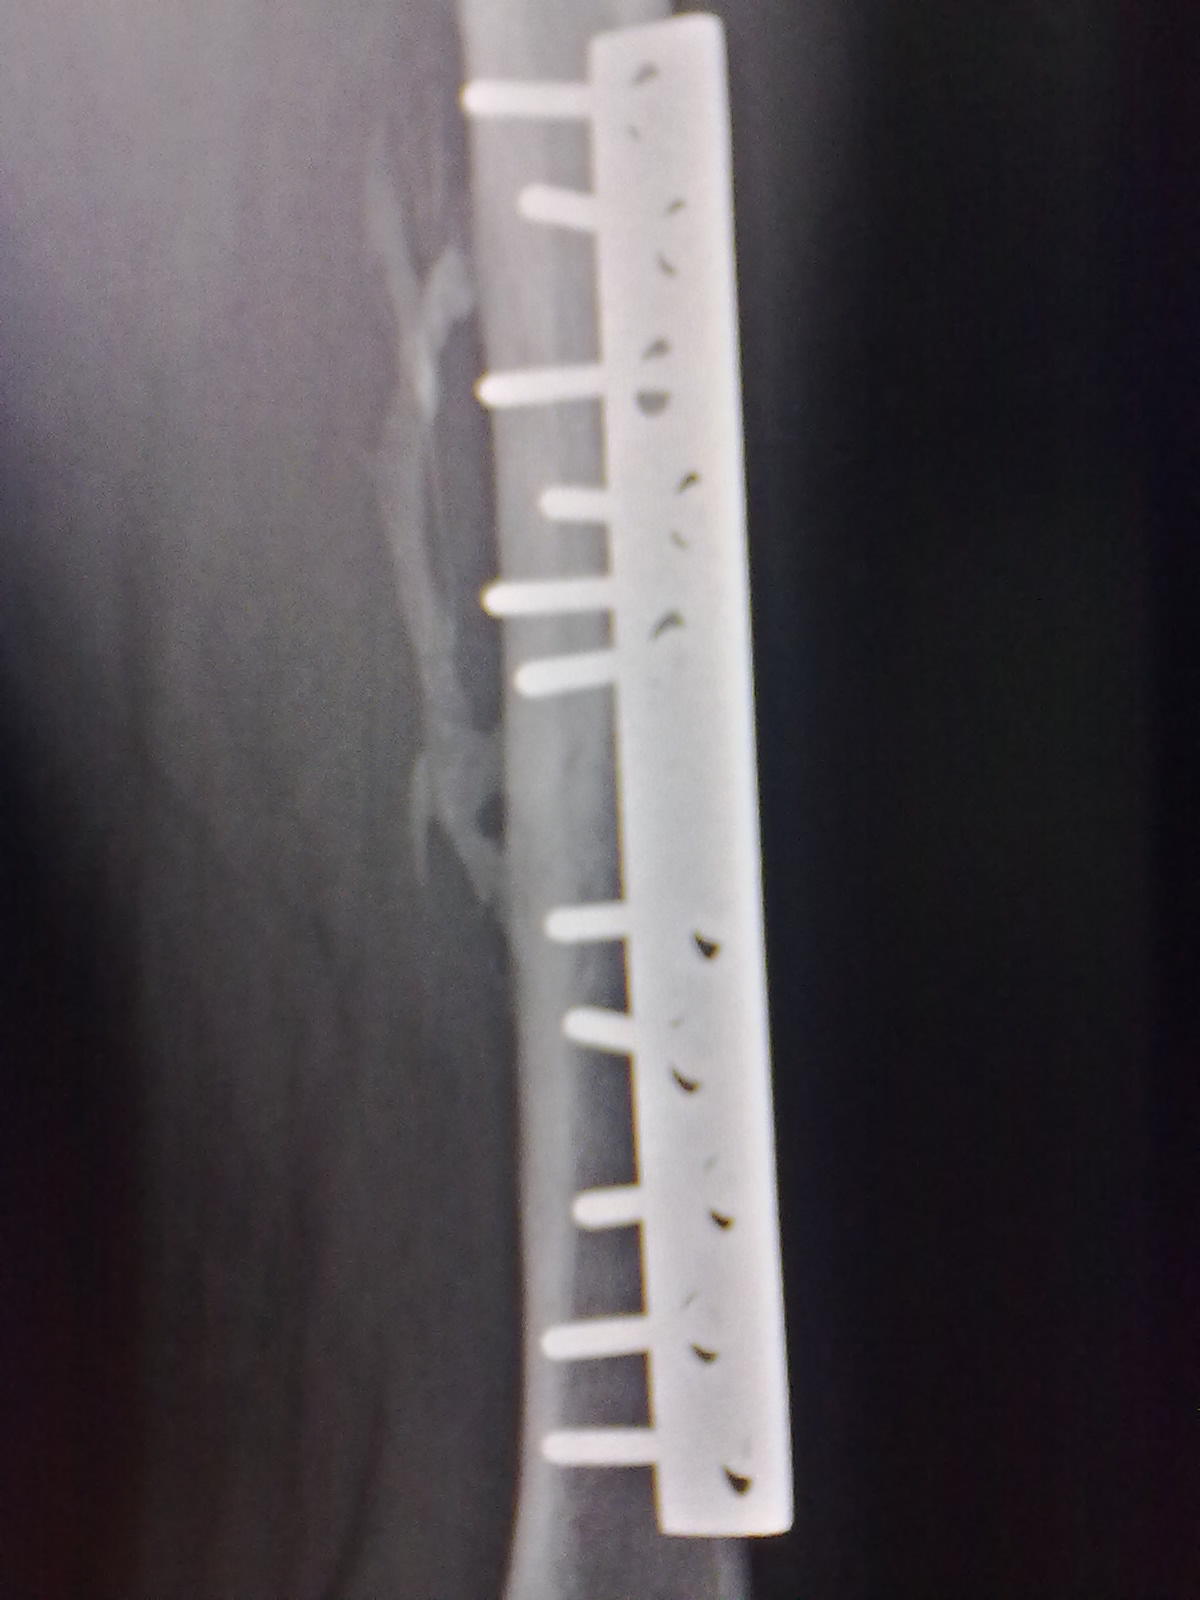

标题: X7065:M,30Y。股骨骨折内固定术后5个月复查片。 [打印本页]

标题: X7065:M,30Y。股骨骨折内固定术后5个月复查片。

外生骨痂还是骨化性机炎?

外骨痂形成。

不好鉴别,需要老片(3-6周时)对比。

二者都有

外骨痂与骨化性肌炎,都能解释。随骨折愈合可消失。

外骨痂及骨化性肌炎。

可能两者介有之。

骨化性肌炎

骨化性肌炎可能。

考虑外骨痂,与临床较相符。

外骨痂及骨化性肌炎两者有之。